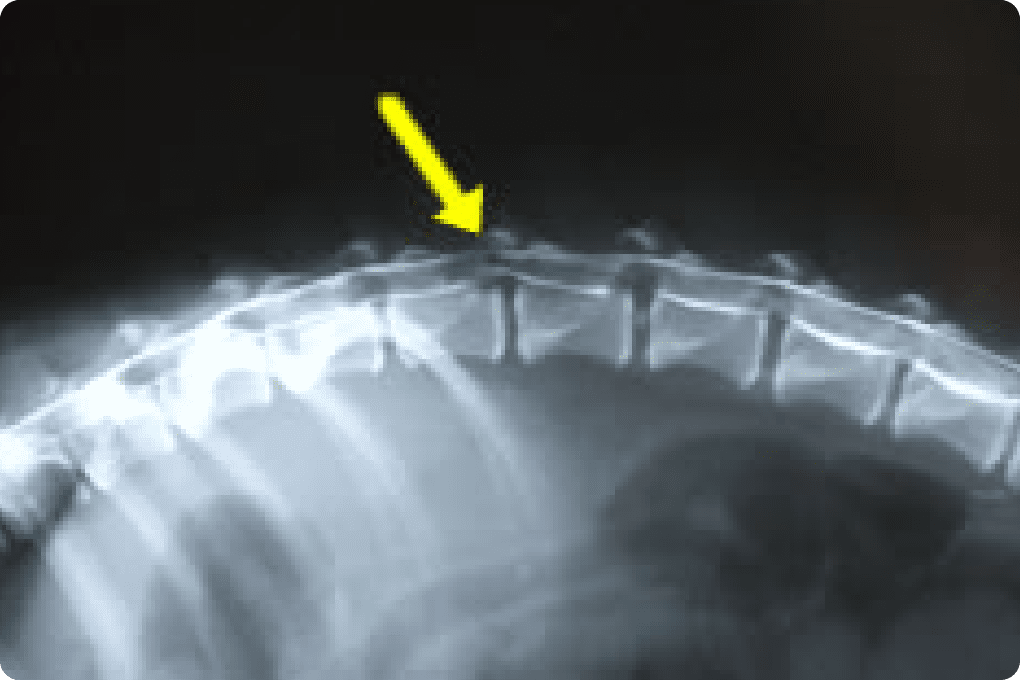

椎間板ヘルニア